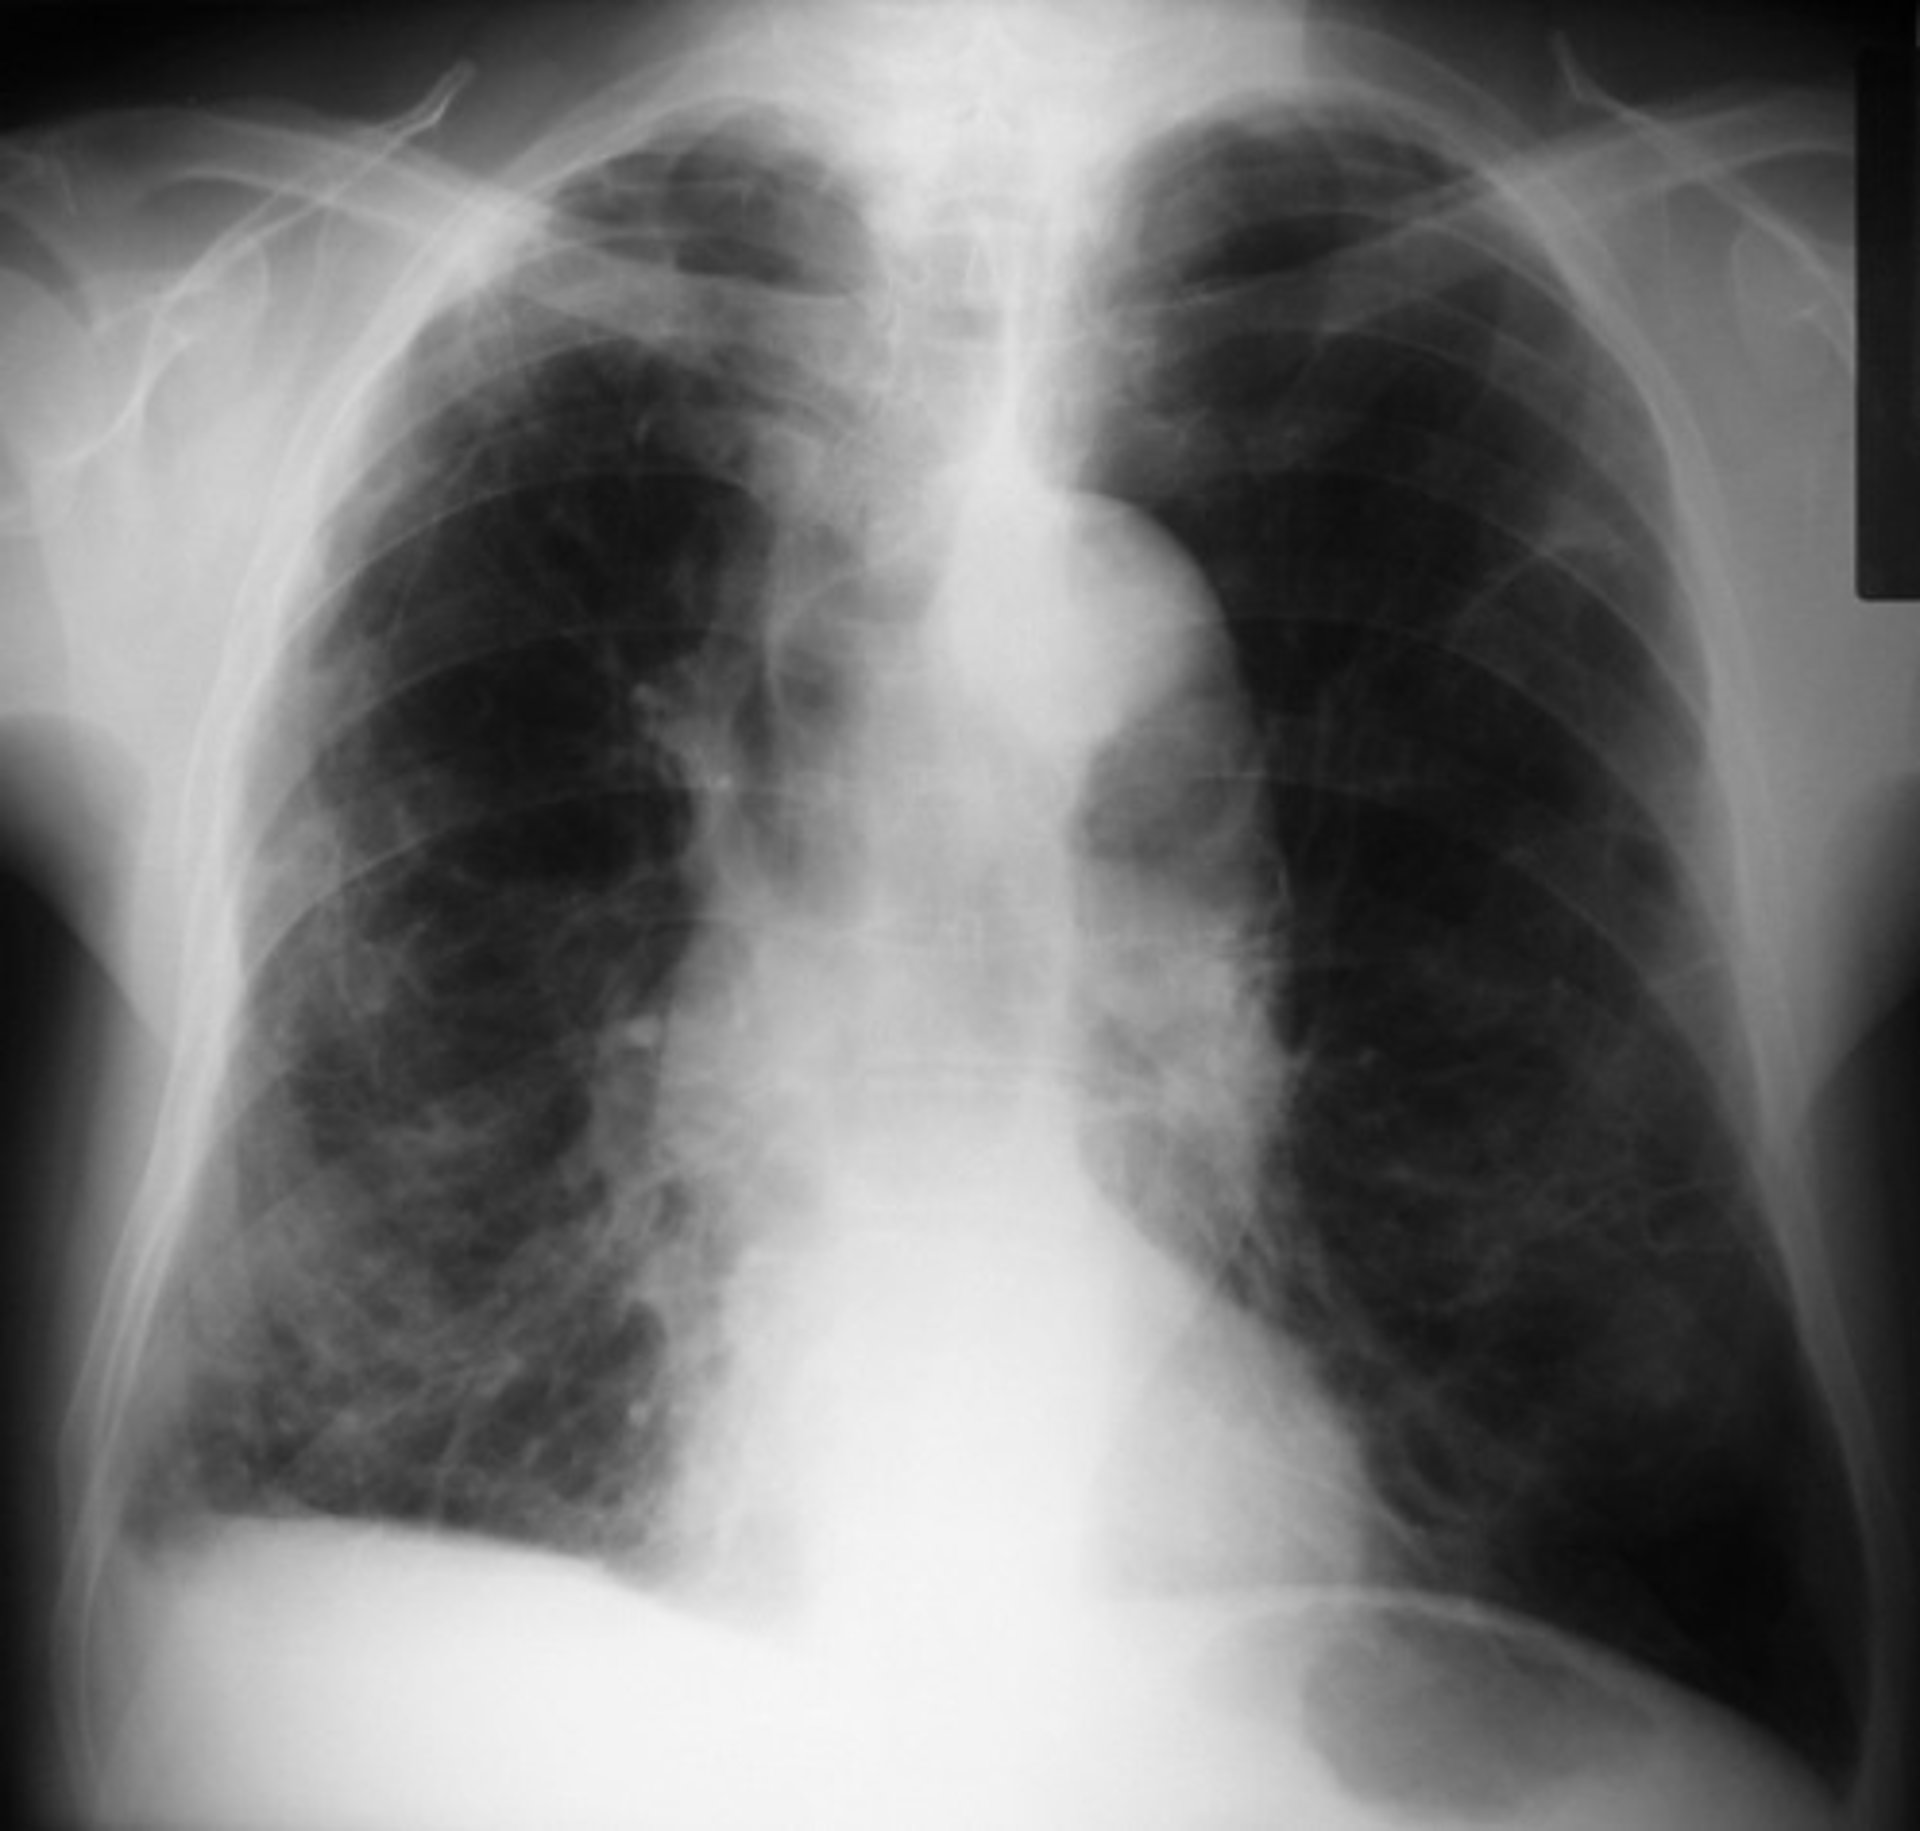

Abren nuevas vías para terapias contra infecciones respiratorias

EPOC

Una investigación liderada por el Instituto de Agrobiotecnología (IdAB), centro mixto del Consejo Superior de Investigaciones Científicas (CSIC), la Universidad Pública de Navarra (UPNA) y el Gobierno de Navarra, ha identificado, a través de una metodología pionera, elementos bacterianos implicados en la infección causada por un patógeno que coloniza las vías respiratorias de pacientes de EPOC (enfermedad pulmonar obstructiva crónica).

Este trabajo ha aplicado la metodología TREP al estudio de la arquitectura genética de la invasión intracelular causada por el patógeno respiratorio Haemophilus influenzae, colonizador de las vías aéreas de pacientes respiratorios crónicos y al que se asocia con el empeoramiento prolongado de los síntomas de la EPOC. "Este patógeno invade el epitelio respiratorio, que es el tejido que recubre el tracto respiratorio y actúa como una barrera de protección de las vías respiratorias, y la infección que causa escapa a la respuesta inmune y a la intervención terapéutica durante la infección crónica _explica Junkal Garmendia_. Gracias a ello, el patógeno persiste".